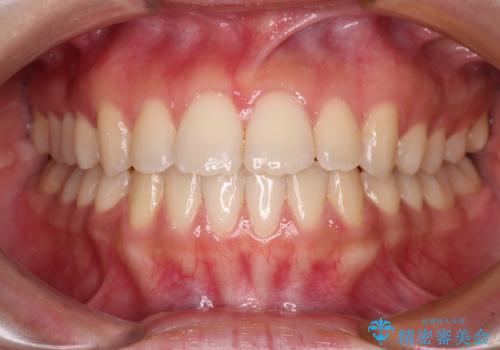

- 前歯2本が飛び出してることを気にして来院された患者様です。

全体的に黄ばんだ歯の色も気になるとのことで、マウスピース矯正により飛び出した前歯を治しつつ、ホームホワイトニングを併用して黄ばみを解消していくこととしました。

歯と歯の間を削ることで、飛び出した前歯が引っ込み、スッキリとした口元となりました。

歯の黄ばみも改善され、明るい歯並びとなりました。